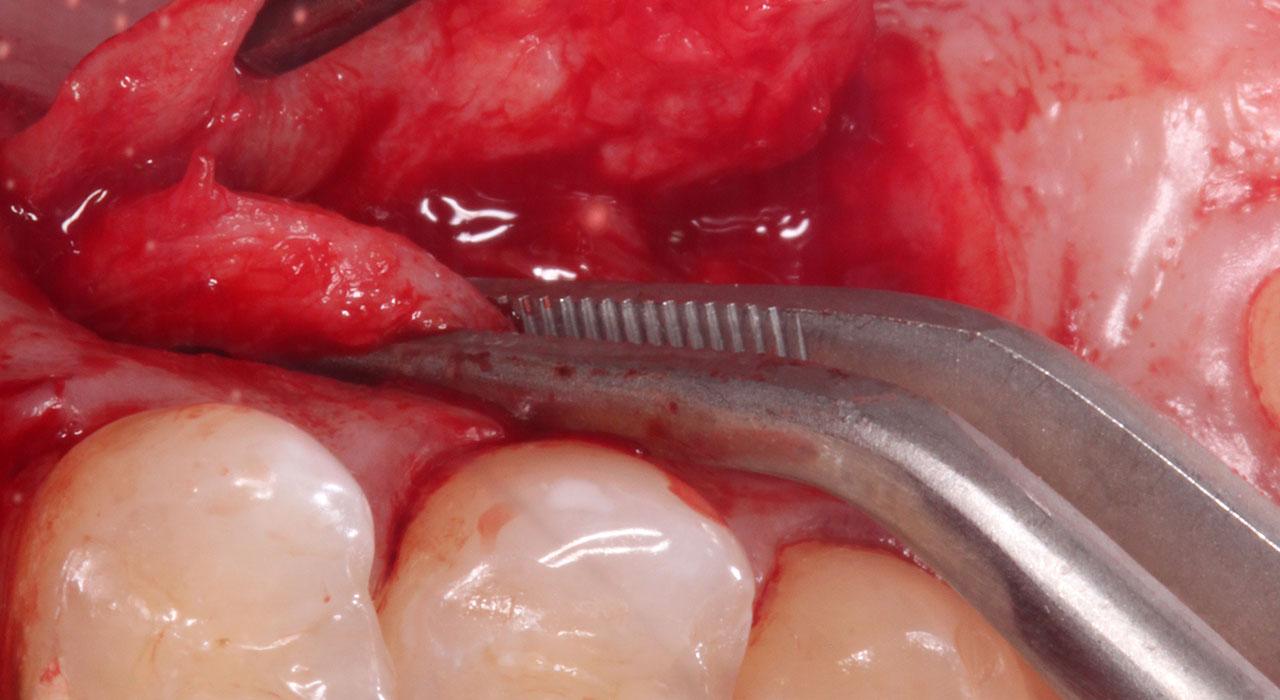

- Injerto de encía